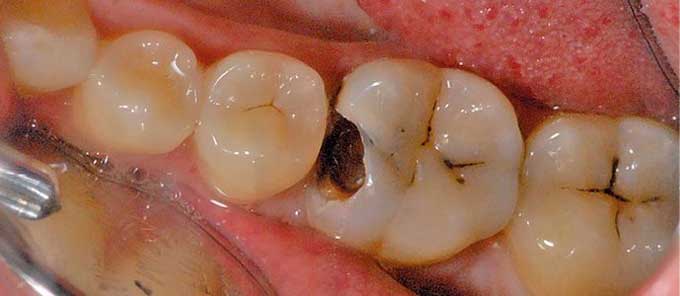

Пульпит развивается вследствие попадания инфекции в пульпарную камеру (полость). Вредоносные микробы (лактобактерии, стрептококки, стафилококки) «переселяются» в пульпу из глубокого кариозного очага. Пути проникновения бактерий бывают различными: дентинные канальца, трещины на эмали и пр.

- Глубокий кариес. Когда кариесогенные микроорганизмы попадают к корням зуба, они доходят до пульпарной камеры.

- Нелеченый кариес. В кариозной полости формируются условия для размножения и дальнейшего распространения патогенной микрофлоры. Через какое-то время микроорганизмы попадают в пульпу, приводя к ее воспалению.

Пульпит зуба из-за низкого качества лечения кариеса

Некачественное лечение кариеса может стать причиной развития пульпита. Для того чтобы вылечить кариозный зуб правильно, специалист при работе должен удалить все поврежденные болезнью ткани, а затем проверить качество выполненных манипуляций специальным кариес-детектором. Если была пропущена, хоть одна зона с разрушенными тканями — препарат окрасит ее в яркий цвет. Однако некоторые специалисты пренебрегают этапом проверки и обрабатывают зуб без использования препаратов-детекторов.

Такой недобросовестный подход чреват рецидивом кариеса: болезнь продолжит развиваться и разрушать дентин, и в конечном итоге бактерии проникнут и в пульповую камеру, вызвав пульпит зуба.